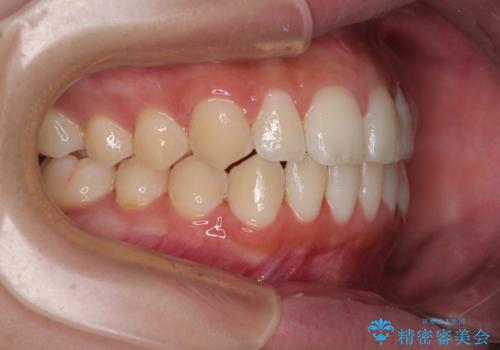

- 今回は「下の前歯のデコボコを治したい」と来院された患者様の症例をご紹介します。

診察してみると、下の前歯が並ぶためのスペースが足りないことが、歯並びがデコボコしている原因でした。

そこで今回は、以下の2つの方法を組み合わせて治療を行いました:

下の前歯の歯と歯の間をわずかに削ってスペースを作る(IPR)

奥歯を後ろに動かして、前歯が並ぶためのスペースを確保する

この計画により、デコボコだった下の前歯はしっかりと並び、わずか1年で治療を終えることができました